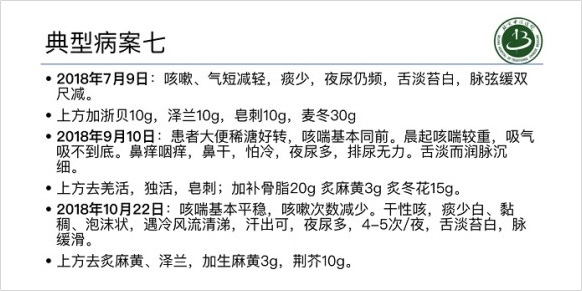

특발성폐섬유증과 같은 간질성폐질환은 예후가 좋지 못하다고 알려진 병입니다. 하지만 한약 치료를 통해 이 병을 극복하려는 노력이 진행되고 있습니다.

이사무 선생의 진료실에서

이사무 선생의 진료실에서